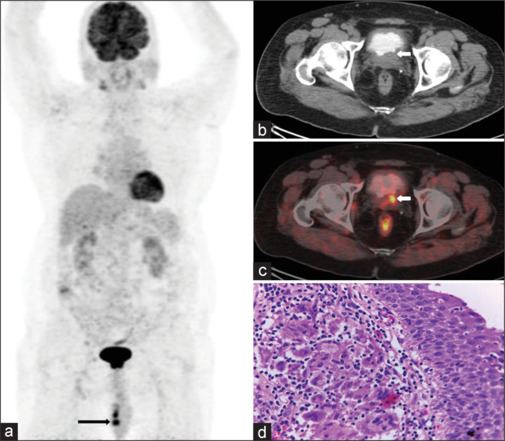

Bacillus Calmette-Guërin (BCG) has been traditionally used as a vaccine against tuberculosis (TB), which contains live, attenuated strain of Mycobacterium bovis. However, intravesical BCG administration has been used as an immunological treatment of superficial bladder cancer. Complications after bladder instillation of BCG are rare. We report a case of carcinoma urinary bladder with histopathologically proven granulomatous epididymo-orchitis (TB) after treatment with intravesical BCG.